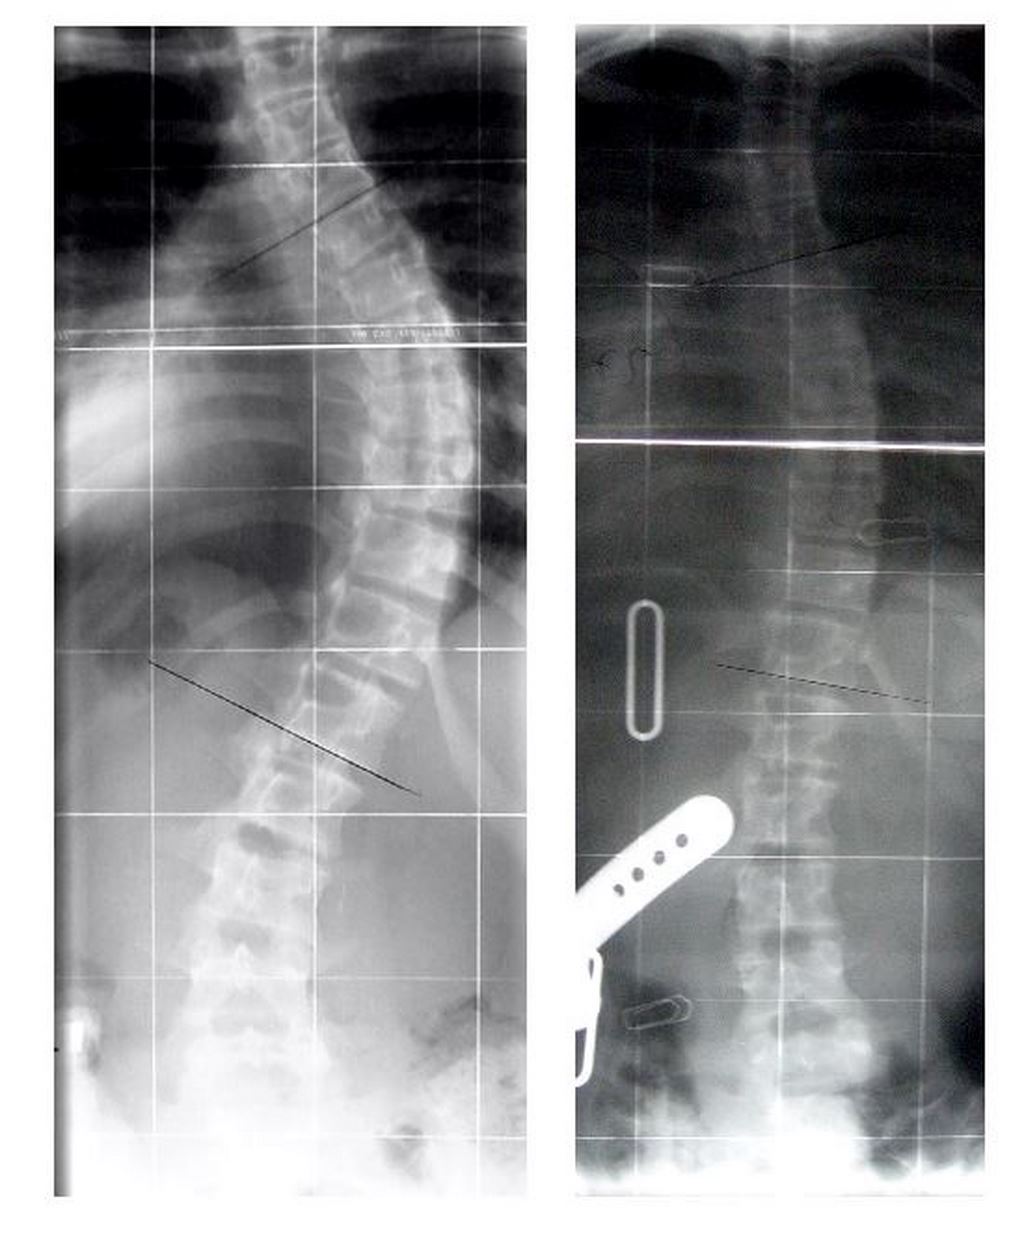

Jeżeli kąt skrzywienia przekroczy 25 º lub gdy następuje duża progresja przy niższych wartościach kątowych zalecaną metodą leczenia jest stosowanie ortezy tułowia typu Rigo Cheneau. Gorset jest indywidualnym zaopatrzeniem ortopedycznym. Jego działanie polega na zastosowaniu trójwymiarowej korekcji deformacji kręgosłupa opierającej się o trójpunktowy rozkład sił oddziałujących na tułów. Korekcję uzyskuję się poprzez zastosowanie pelot uciskowych i obszarów odciążających w płaszczyźnie czołowej, poprzecznej oraz strzałkowej. Gorset korekcyjny umożliwia dwa rodzaje korekcji – czynną i bierną. Korekcja czynna przeciwdziała progresji skrzywienia oraz wzmacnia prawidłową strukturę mięśniową. Korekcja bierna umożliwia tzw shift czyli przesunięcie boczne tkanek za pomocą pelot oraz zmniejsza patologiczne ustawienie kręgów.

Gorsety korekcyjne stosuje się również w przypadku choroby Scheurmanna. Jest to schorzenie które dotyka najczęściej chłopców w okresie dojrzewania. Objawia się pogłębioną kifozą piersiową. Na obrazie RTG możemy zaobserwować zklinowacenie kręgów piersiowych wynikające z uszkodzenia płytek granicznych. Zadaniem gorsetu jest zatrzymanie progresji choroby poprzez zastosowanie komponenty wyprostnej. Poza gorsetami korekcyjnymi w naszym zakładzie zaopatrujemy dzieci z rdzeniowym zanikiem mięśni, przepukliną oponowo-rdzeniową oraz porażeniem dziecięcym.

W Pomorskim Centrum Protetyki i Ortotyki Narządu Ruchu Ortomax gorsety korekcyjne wykonujemy metodą CAD/CAM. Na pierwszej wizycie pobierany jest skan pacjenta oraz badanie wykonywane przez fizjoterapeutę. Na kolejnej następuje już przymiarka gorsetu połączona z odbiorem. Dzięki zastosowaniu najnowszych technologii nasze gorsety są lepiej dopasowane niż te wykonywane metodą tradycyjną (gipsową). Lokalizacja pelot jest bardziej precyzyjna poprzez zestawienie skanu pacjenta z jego zdjęciem RTG a narzędzia wykorzystywane przy projektowaniu gorsetów pozwalają na uzyskanie większej korekcji skrzywienia przy jednoczesnym zachowaniu wysokiego komfortu. Dużą wagę przykładamy również do jak najniższej wagi ortezy dlatego termoplasty wykorzystywane do produkcji gorsetów są wysokiej jakości. Pozwala to na odpowiednie ich rozciągnięcie podczas termoformowania – uzyskujemy zatem produkt lekki a zarazem odpowiednio sztywny do transferu sił korekcyjnych.